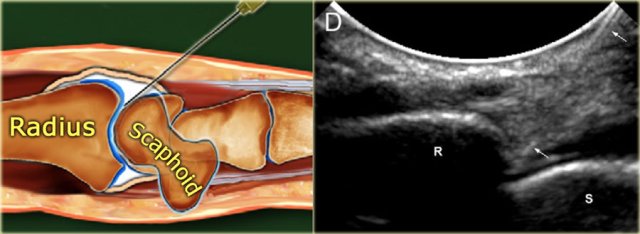

Radiocarpal joint

The patient is supine with the wrist resting flexed over a 45◦ sponge or a rolled-up towel.

In some cases it may be helpful to hold the wrist in ulnar deviation in order to open the joint space even more.

The space between the radius and the scaphoid is identified on ultrasound.

A 23-25-gauge, 30 mm needle is advanced under ultrasound guidance into the joint directed toward the articular surface of the radius until one feels contact with the radius.

After ensuring that the tip of the needle is free from the radial cartilage 2-4 mL contrast is injected.

The bevel of the needle is facing toward the joint space and the contrast is seen to flow into the joint.